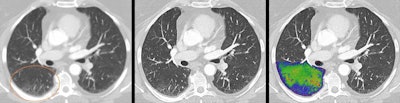

Research had shown that in thoracic imaging, it not only provides sharper images but also could "increase reader confidence" for a diagnosis of interstitial lung disease, he added.

"Of course, further clinical studies will be needed to demonstrate the clinical potential photon-counting has, in differential diagnosis and follow up of lung diseases," Flohr said.